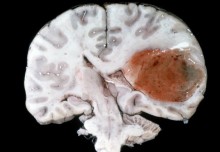

They found no signs of suffering, tissue damage, or infection following catheter implantation.

Lead author Dr Riccardo Secoli, also from Imperial’s Department of Mechanical Engineering, said: “Our analysis showed that we implanted these new catheters safely, without damage, infection, or suffering. If we achieve equally promising results in humans, we hope we may be able to see this platform in the clinic within four years.

Professor Lorenzo Bello, study co-author from the University of Milan, said: “One of the key limitations of current MIS is that if you want to get to a deep-seated site through a burr hole in the skull, you are constrained to a straight-line trajectory. The limitation of the rigid catheter is its accuracy within the shifting tissues of the brain, and the tissue deformation it can cause. We have now found that our steerable catheter can overcome most of these limitations.”